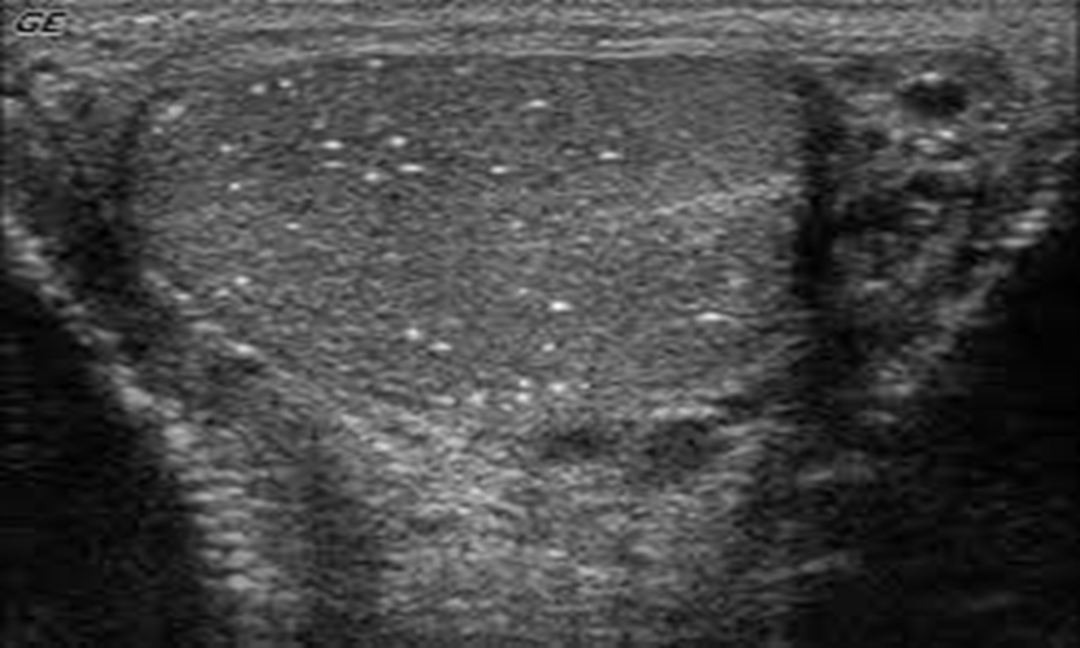

Microlithiasis appears as small non-shadowing hyperechoic foci ranging in diameter from 1-3 mm.